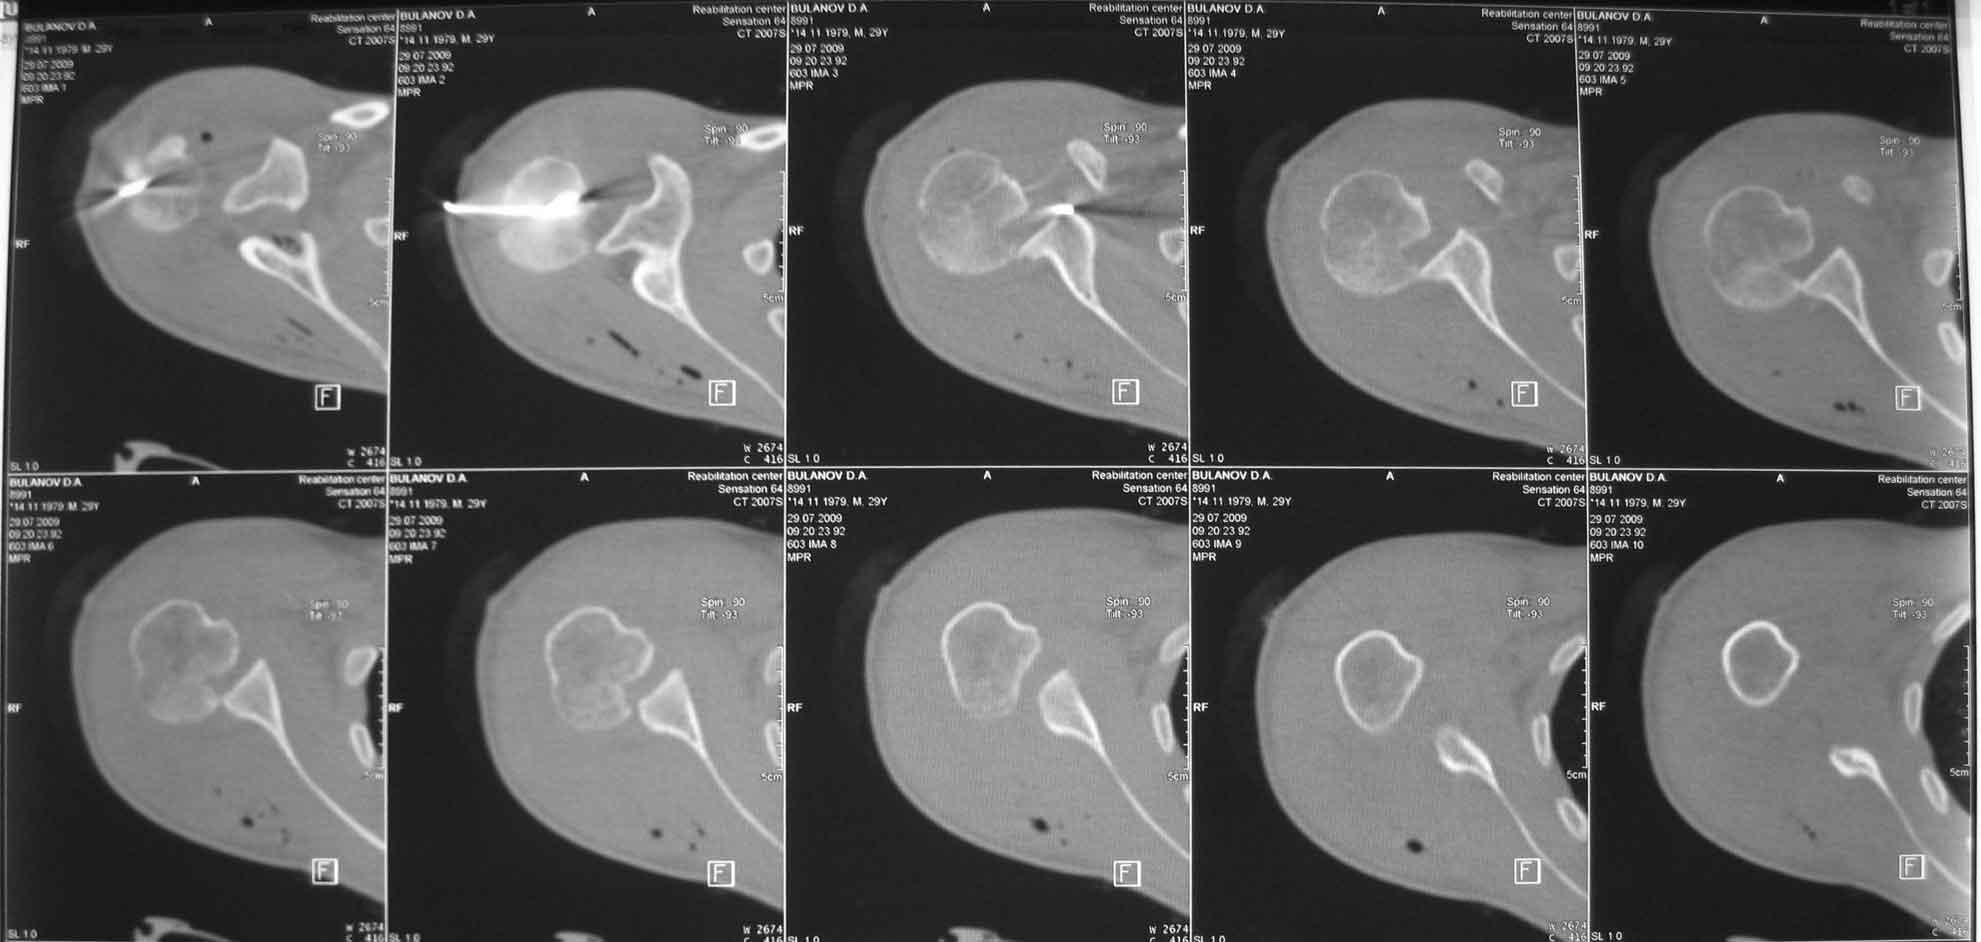

Вот послеоперационная КТ.

Рука в бандаже у живота.

Кликните для загрузки файла 1kt.jpg